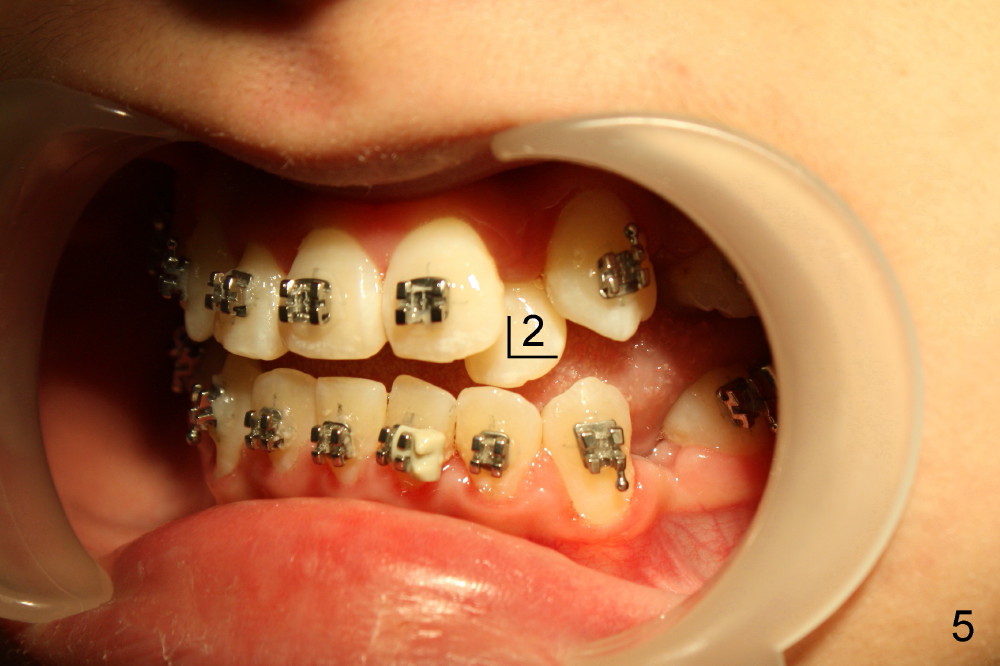

David, 16 years old, has severe crowding, midline deviation (Fig.1: dashed lines), and UL2 complete blockout (Fig.3: 2). Orthodontic treatment starts with extraction of four of the 1st bicuspids (Fig.2,3: .014 Niti).

Five weeks later, .018 ss wires are installed with open coil spring between UL 1 and 3 and power chain between UL 3 and 7 (Fig.4). Three months post-bracketing, space is being created for UL 2 (Fig.5). Four months post-bracketing, a lingual button is placed on UL2 with power chain x7 (Fig.6: sling shot); Pletcher's spring between UL 3 and 7 (^).